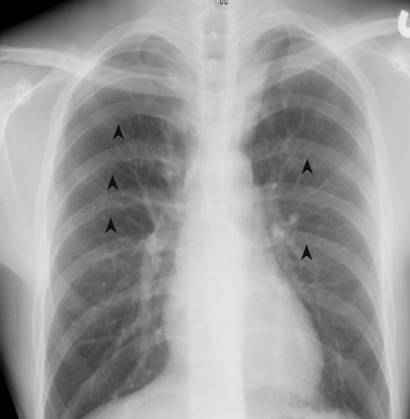

Figure 4

Chest X-ray shows multiple rib notchings (arrowheads).